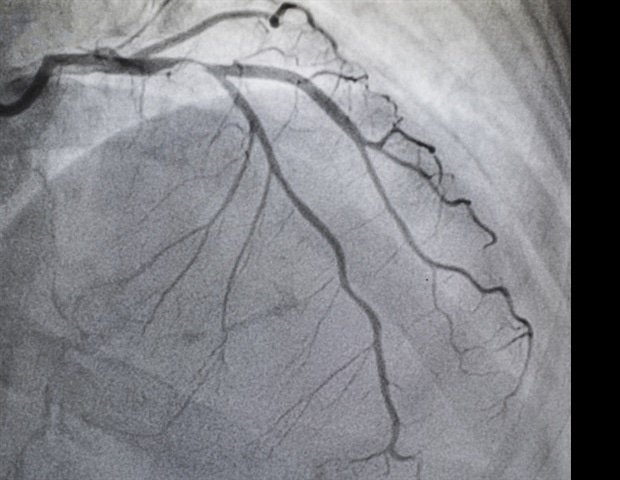

TAVR is a minimally invasive surgery in which a doctor inserts a new heart valve into a blood vessel without opening the chest, whereas SAVR requires open-heart surgery, in which the doctor opens the chest, removes the old valve, and sews in a replacement valve. Over the past decade, clinicians have expanded TAVR from an option for high-risk patients to a first-line treatment for patients at all risk levels.